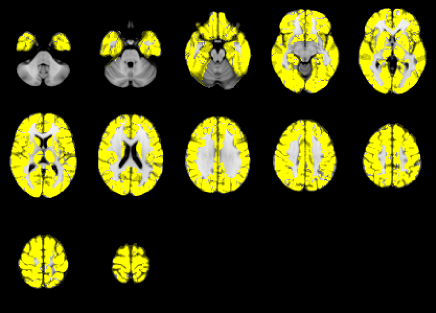

To obtain anatomically defined ROIs, we used the Anatomical Automatic Labeling (AAL) atlas, which gives anatomical parcellation of the whole brain into 45 regions in each hemisphere (Tzourio-Mazoyer et al., 2002). These anatomical regions are listed in Table S1 in the supplement. The number of voxels included in the AAL are approximately 150,000 for each scan, for a total of approximately 22 million data points. Voxel-specific fMRI time series were then extracted based on the subject-specific AAL-derived brain parcellation.

where and are the (normalized) coordinates over the three axes, and are the maximum lengths across the three axes. To avoid identification issues, we set constant across the ROI. We thus need to estimate for each harmonic , for each coordinate and for each ROI . As in the previous sections, each ROI can be estimated independently and the code can be easily parallelized, but the computational and memory demand for each likelihood evaluation allowed only to fit the model for . Figure 7 shows the activated voxels for each ROI with False Discovery Rate (Benjamini and Hochberg, 1995) at assuming independence and spatial dependence. The results for particular areas will be discussed in Section 6.